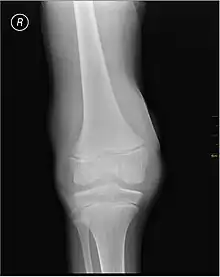

| Lipohemarthrosis (blood and fat in the joint space) seen in a person with a subtle tibial plateau fracture. The arrow indicates a fluid level between the upper fat component and the lower blood component. | |